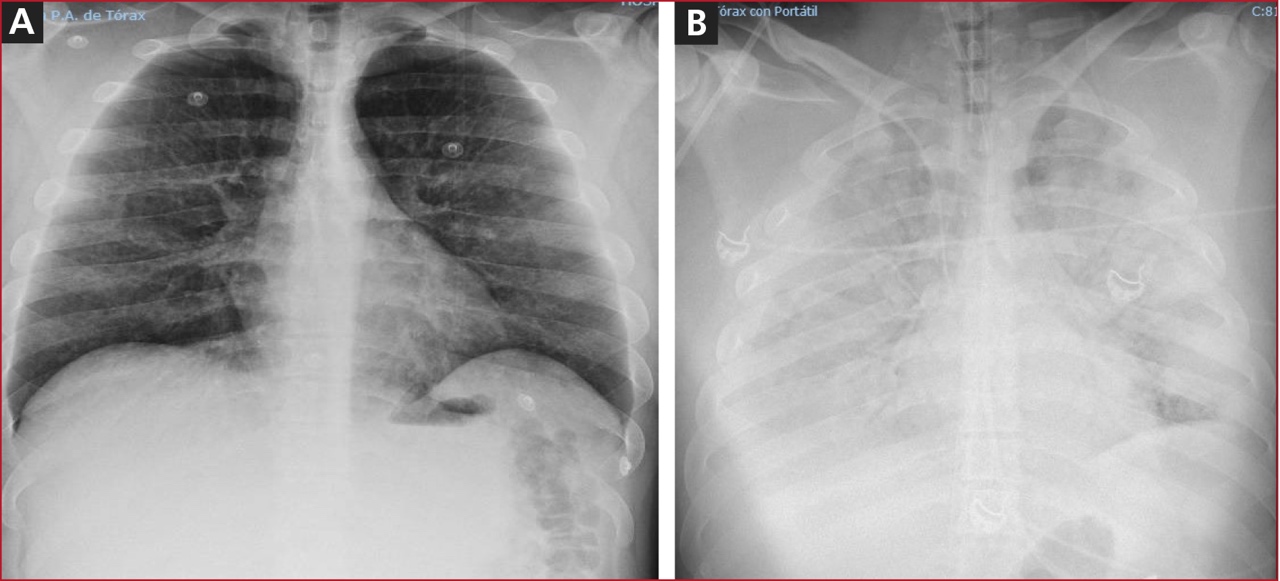

Hombre de 30 años de edad, sin antecedentes patológicos. Limpiando la depuradora de su piscina, inhaló accidentalmente cloro y floculante (sulfato de aluminio-sulfato de amonio). Permaneció aproximadamente 5 minutos en una estancia sin ventilación en contacto con el gas. Comenzó con tos irritativa y disnea que lo obligó a salir al exterior. Acudió al Servicio de Urgencias del hospital con signos de insuficiencia respiratoria hipoxémica, sin respuesta a la oxigenoterapia, ni a los corticoides inhalados e intravenosos. La radiografía posteroanterior de tórax era normal (Figura).

Figura. Radiografía posteroanterior de tórax al ingresar (A) y a las 3 horas (B).

El cuadro clínico progresivo empeoró, con PAFI <70 mmHg, acidosis láctica e hipotensión arterial; por lo tanto, se procedió a la intubación orotraqueal y a la conexión a ventilación mecánica (VM). Se administró bicarbonato 1 M y noradrenalina hasta 0,6 µg/kg/min. Una nueva radiografía posteroanterior de tórax (Figura) reveló un infiltrado alveolo-intersticial bilateral. El hemograma y los estudios de coagulación y perfiles bioquímicos fueron normales. En una ecocardiografía transtorácica, se observó un ventrículo izquierdo no dilatado con fracción de eyección normal y cavidades derechas normales. La ecografía pulmonar mostró abundantes líneas B distribuidas de forma difusa y bilateral.